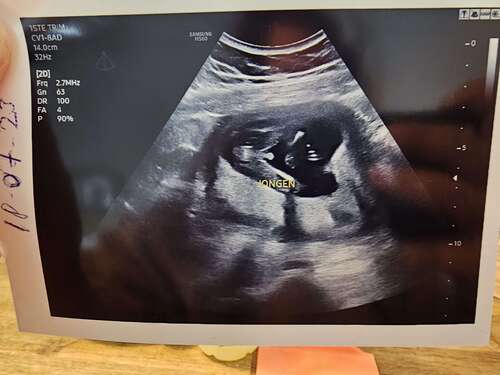

Bij een jongen zijn er testikels met daaraan een penis te zien en bij meisjes is de vagina zichtbaar als kleine drie strepen.

Ik krijg een meisje, dan kan je vergelijken! Ik denk eigenlijk dat jij een jongetje krijgt馃き馃挋 Maar kan er ook volledig naast zitten 馃